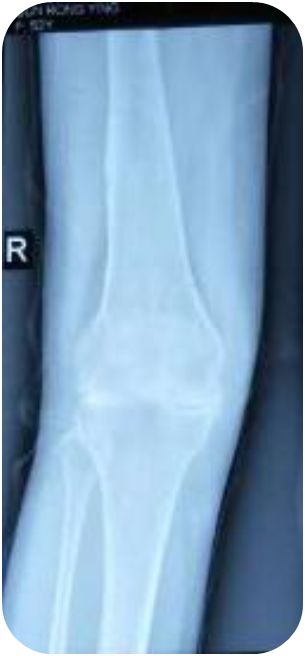

患者在住院期间,风湿病科主管医师普勇斌一直精心诊治、丁珊医师行针灸治疗,同时护士予中药封包、中药热奄包等治疗,但患者症状缓解不明显,查看患者右膝关节正侧位片发现:患者右膝关节骨质破坏严重,关节间隙明显变窄模糊,追问患者,患者诉3年前右膝就伸不直了,多家医院都考虑关节畸形严重,建议患者行膝关节人工关节置换,但患者出于经济情况等多方面考量坚持保守治疗,后由丁珊医师详细讲解了针刀治疗的风险及术后注意事项,患者签署了操作同意书,予患者行右膝小针刀松解术。

患者治疗前后膝关节X线片对比